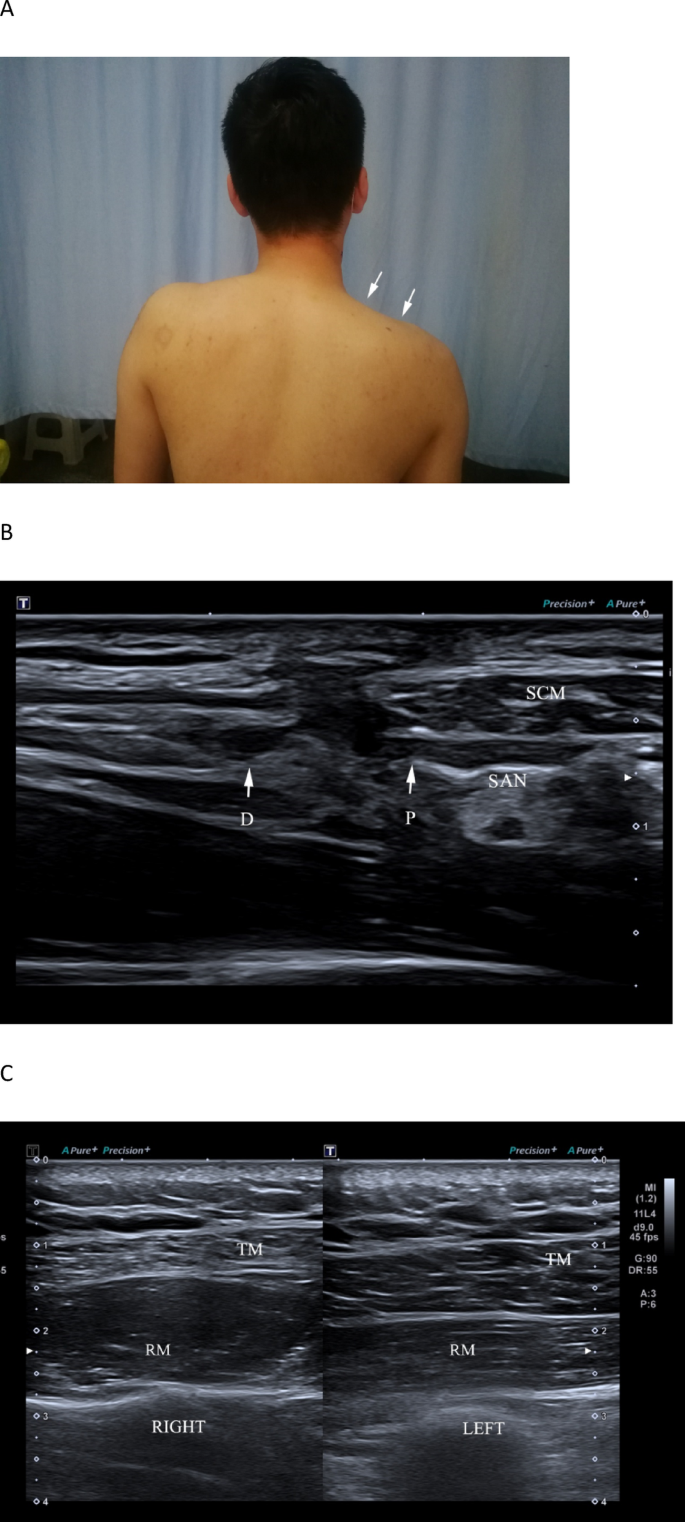

From July 2022 to March 2024, 12 patients were diagnosed with SAN injury through HRUS, confirmed by surgery or MRI. All patients had a history of neck surgery or trauma, including 7 cases of cervical lymph node biopsy, 3 cases of vascular anomaly surgery, and 2 cases of knife injury. Among these, 5 injuries were in segment S3, and 7 were in segment S2. Pathologic SANs showed characteristic changes: diffusely increased intraneural echogenicity consistent with neural fibrosis (the so-called “white nerve”), loss of normal fascicular definition, and caliber alterations. In cases with discontinuity, HRUS demonstrated complete nerve rupture with retracted proximal/distal stumps and bulbous traumatic neuroma at the ends in some patients, often accompanied by trapezius muscle atrophy and increased echogenicity of the affected muscle (Figs. 5, 6, Supplementary Video S1 and Supplementary Video S2). All 12 patients underwent surgical treatment.

A 33-year-old male complained of right shoulder pain, weakness, and numbness four months after a stab injury. A A clinical photograph demonstrates right shoulder drooping. B Ultrasonography shows complete transection of the spinal accessory nerve (SAN); P denotes the proximal stump and D the distal stump. The adjacent sternocleidomastoid muscle (SCM) exhibits focal fibrous disruption. C Ultrasound of the trapezius (TM) on the affected side demonstrates denervation atrophy (thinning and increased echogenicity), with the underlying Rhomboids (RM) labeled for orientation.

Supplementary Video 2. A 33-year-old male complained of right shoulder pain, weakness, and numbness four months after a stab injury. Ultrasonography shows a rupture of the spinal accessory nerve (SAN) at S1 and localized fibrous rupture of the sternocleidomastoid muscle. SAN P, the proximal end of the ruptured spinal accessory nerve; SAN D, the distal end of the ruptured spinal accessory nerve